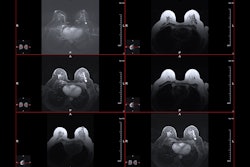

Delaware leads the U.S. in the incidence of triple-negative breast cancer and advanced breast cancer diagnosed at a younger age, ChristianaCare researchers highlighted. Areas of higher intensity, which are visualized in this map with brighter shades of red, have higher historical rates of triple-negative breast cancer diagnosed at an advanced stage among women younger than 50 years relative to other areas within New Castle County, Delaware.ChristianaCare